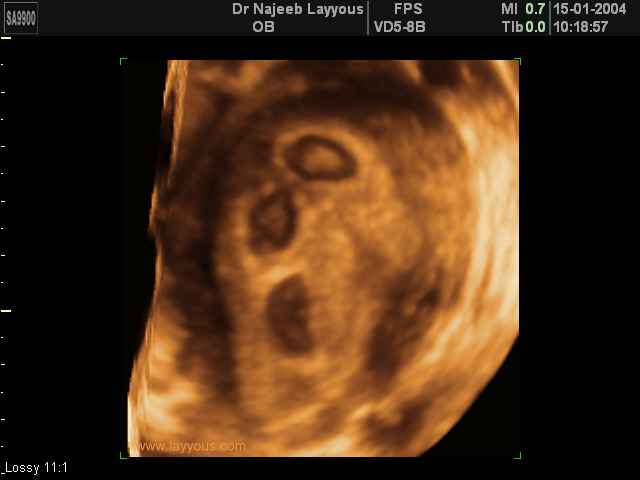

- صور لتوائم

صور لتوائم بجهاز الالتراساوند ثلاثي الأبعاد | الدكتور نجيب ليوس